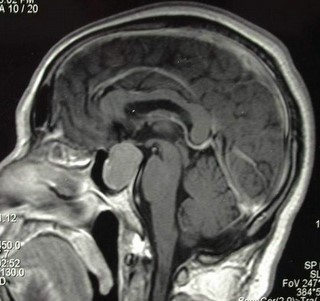

门诊碰到一位男性患者,一年前视力突然出现不明原因的视力下降,伴有管状视野,视线被局限在前方很小的角度内。在外地眼科就诊为球后视神经炎,一直保守治疗无效,病情反而逐渐加重。后经CT、MRI检查证实是垂体瘤压迫视神经所致,遂来我院神经外科治疗。王振宇主任经鼻为患者成功实施了垂体瘤切除手术,不仅避免了开颅,而且患者第二天即恢复了双眼正常视野。

垂体瘤是一种较为常见的颅内肿瘤,约占颅内肿瘤的10%。垂体是颅内发生肿瘤最常见的部位。垂体正上方为视神经、视交叉,与垂体相距约1厘米。垂体瘤较大时极易压迫相邻的视神经、视交叉,从而导致视力和视野障碍。